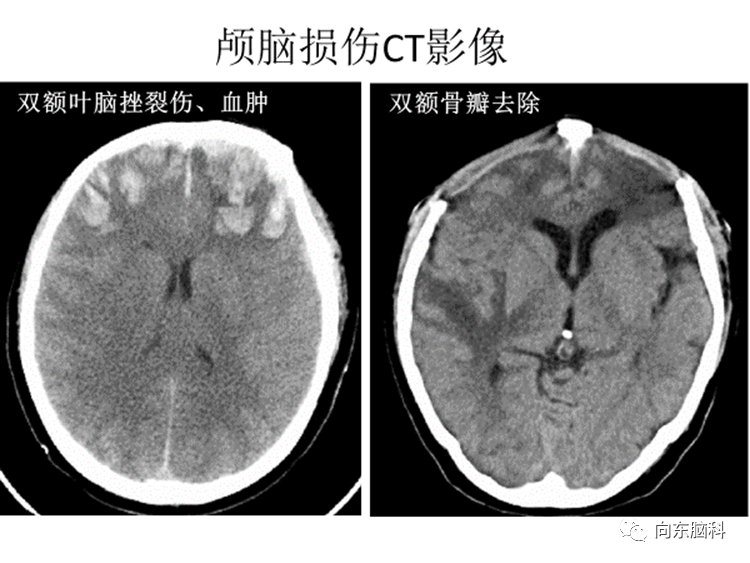

例如上图这位患者因为车祸致致双额叶脑挫裂伤,脑出血,脑水肿、导致颅内高压,为了挽救他的生命,手术去除了双侧的额骨,等到患者病情稳定和好转,脑水肿减退,颅内压恢复正常以后,CT扫描3D影像重建可见双侧额部明显的凹陷